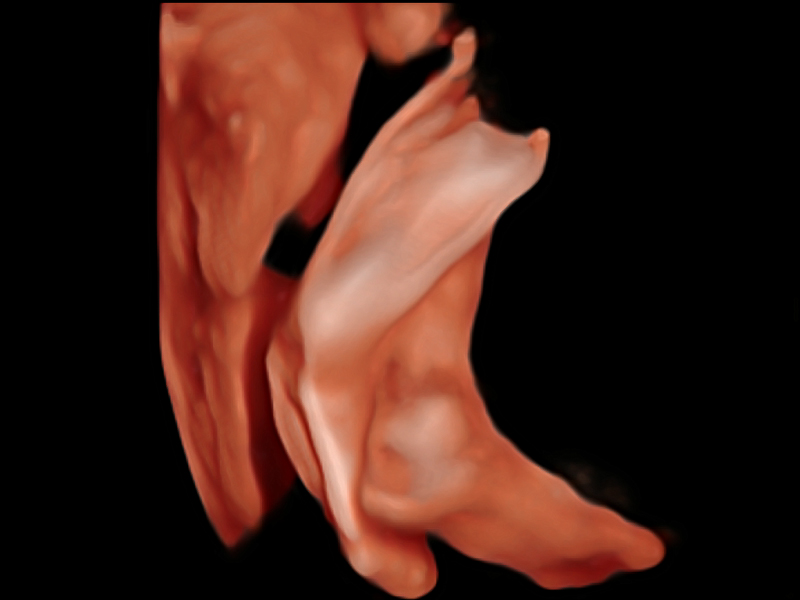

S-Fetus基于大數(shù)據(jù)深度學習算法,能夠幫助您在產(chǎn)前篩查過程中智能識別胎兒標準切面、自動測量并錄入報告。一個按鍵,即可智能、精準、高效地獲取胎兒生理指標,極大簡化您的產(chǎn)科檢查操作。

可快速對產(chǎn)科掃查切面完成胎兒生理學參數(shù)的自動測量,減少操作者按鍵次數(shù),大幅提升檢查效率。

自動識別頸項透明層并獲得NT值,為早孕胎兒畸形篩查提供有效測量工具,提高診斷效率和診斷信心。